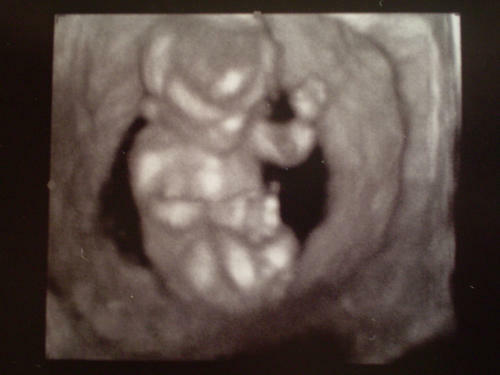

Panda, nagyon szép babád van!